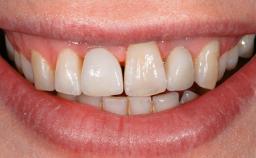

A 77-year-old male patient was referred for the management of frequent and repeated acrylic fracture of his existing mandibular fixed full-arch implant-supported metal/acrylic prosthesis. He also complained about softtissue soreness and the lack of retention and stability of his maxillary removable partial metal/acrylic prosthesis. Both prostheses had been delivered two years previously as part of his full-mouth rehabilitation (caries, tooth wear, tooth fracture). His medical history revealed high blood pressure, controlled with the use of antihypertensive medication.

Lip Line No exposure of papillae Exposure of papillae Full exposure of mucosa margin

Esthetic Risk Low